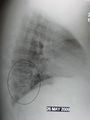

A lateral CXR showing right lower lobe pneumonia

Right upper lobe pneumonia as marked by the circle.